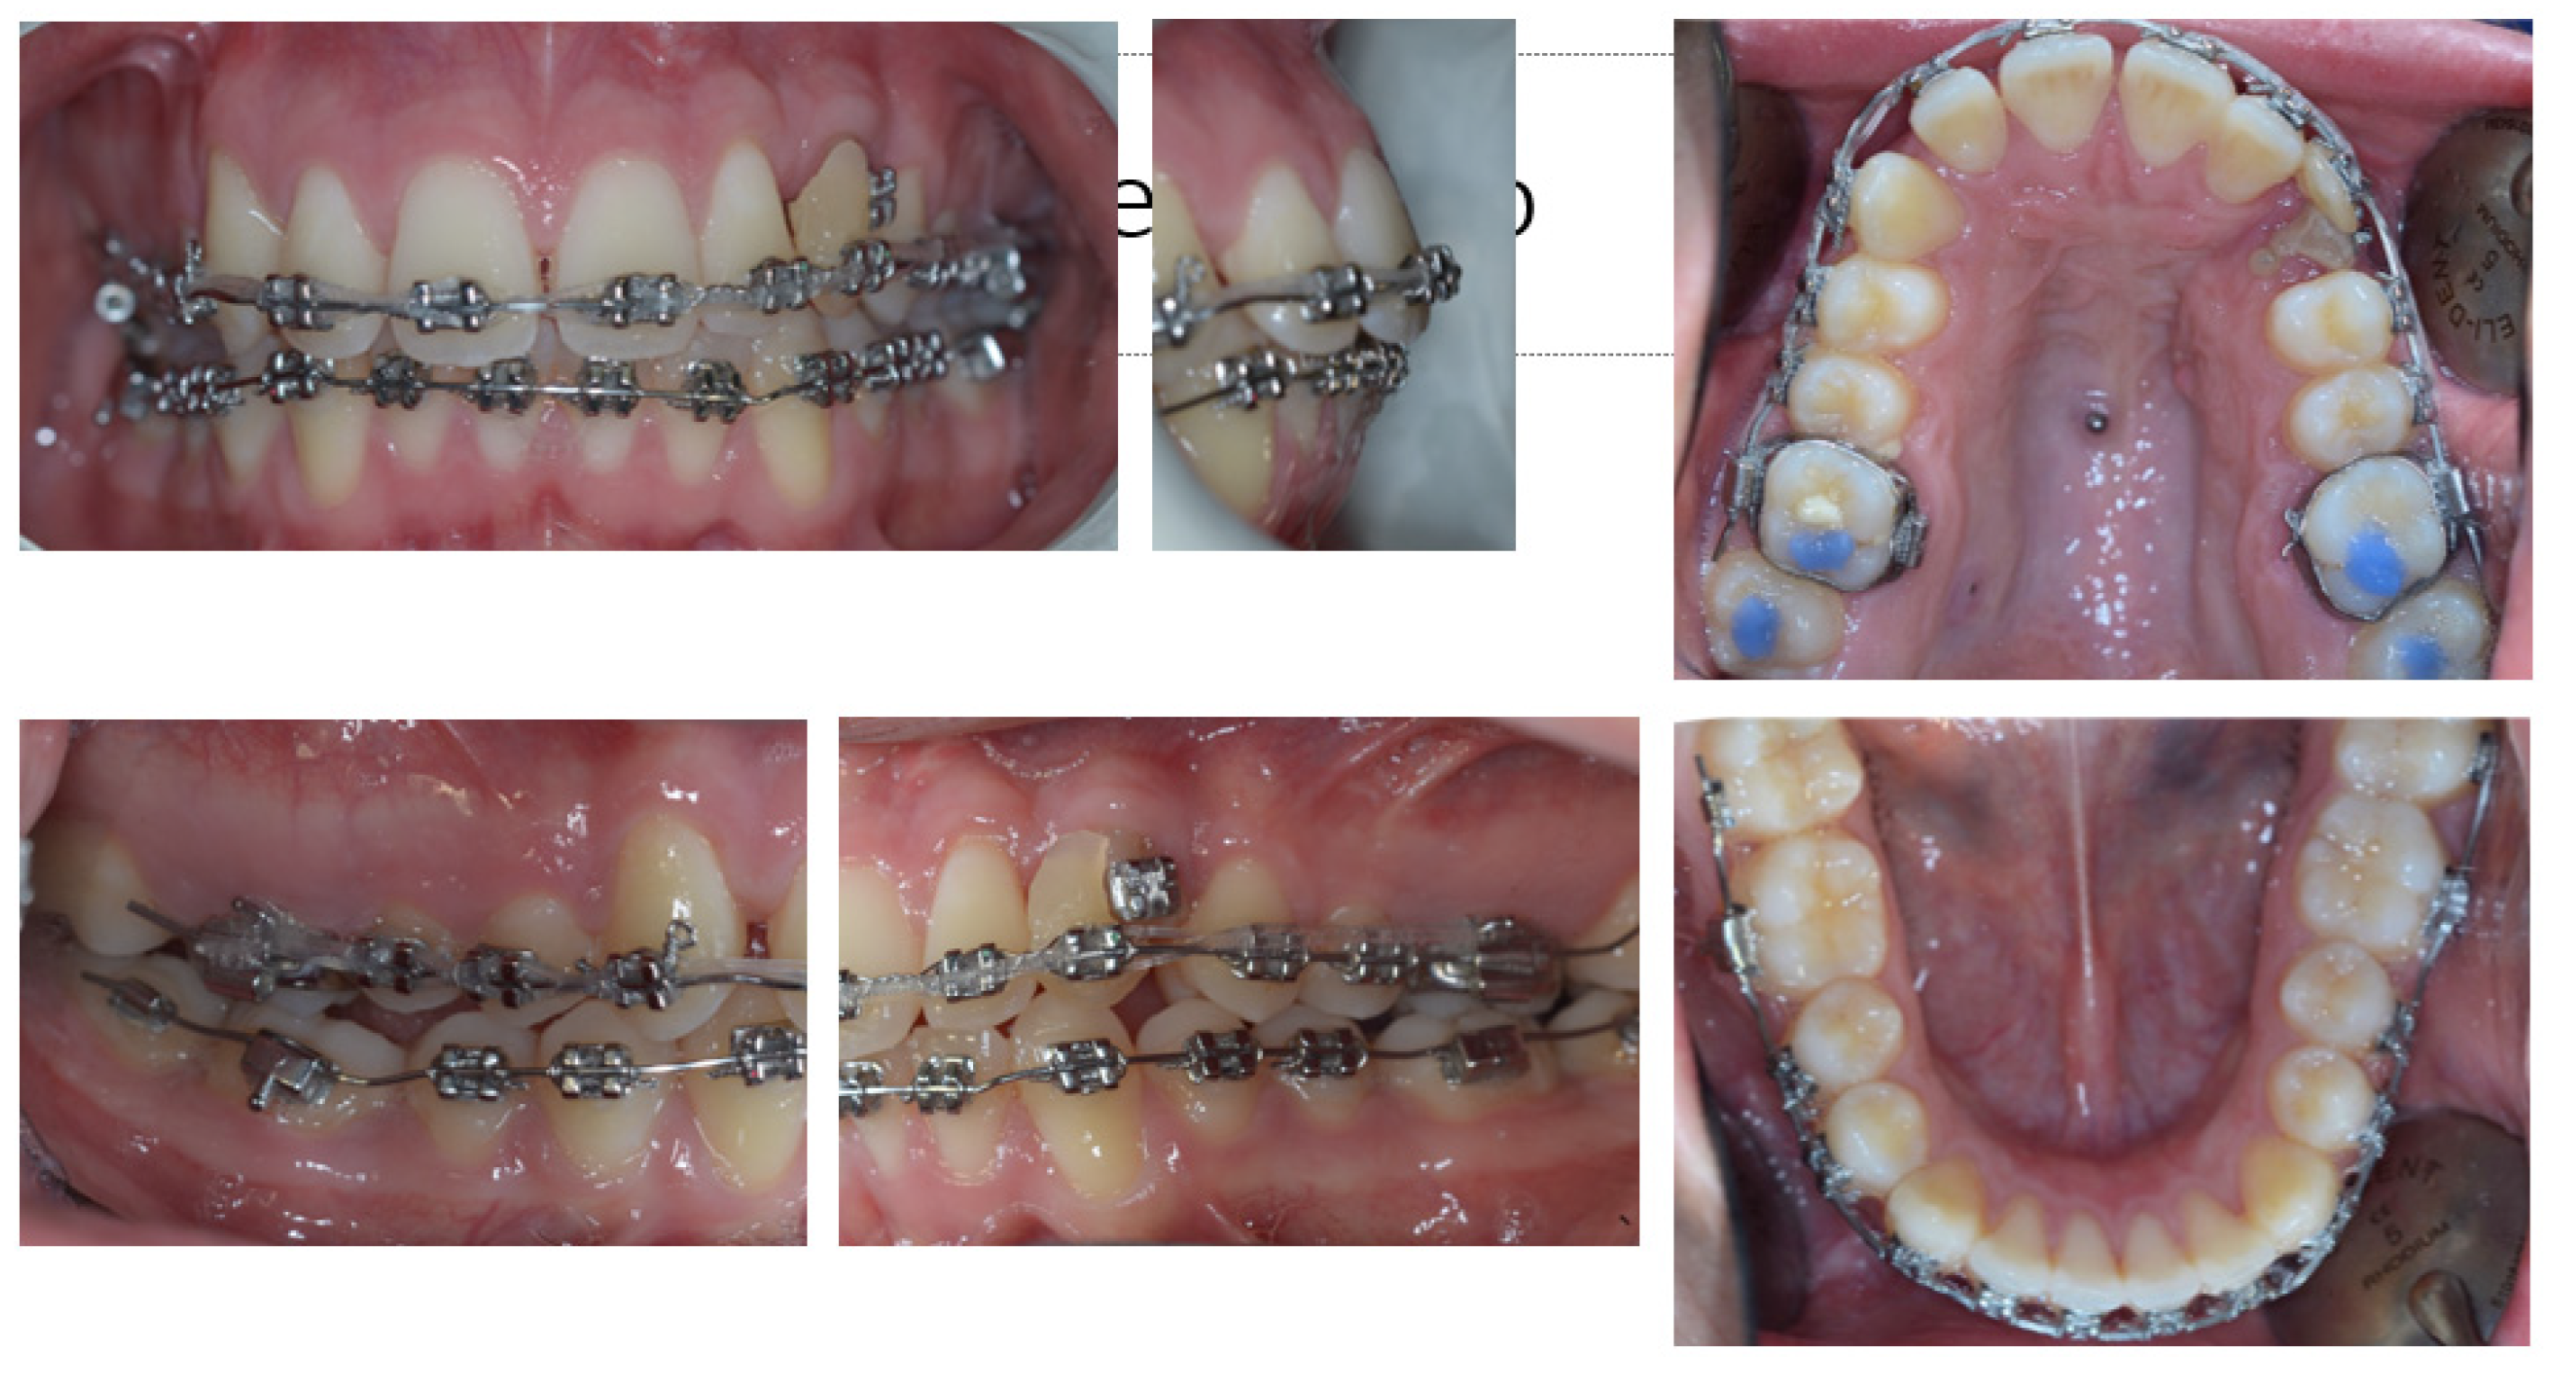

2. Patient Information—Case Presentation

2.1. Clinical Findings